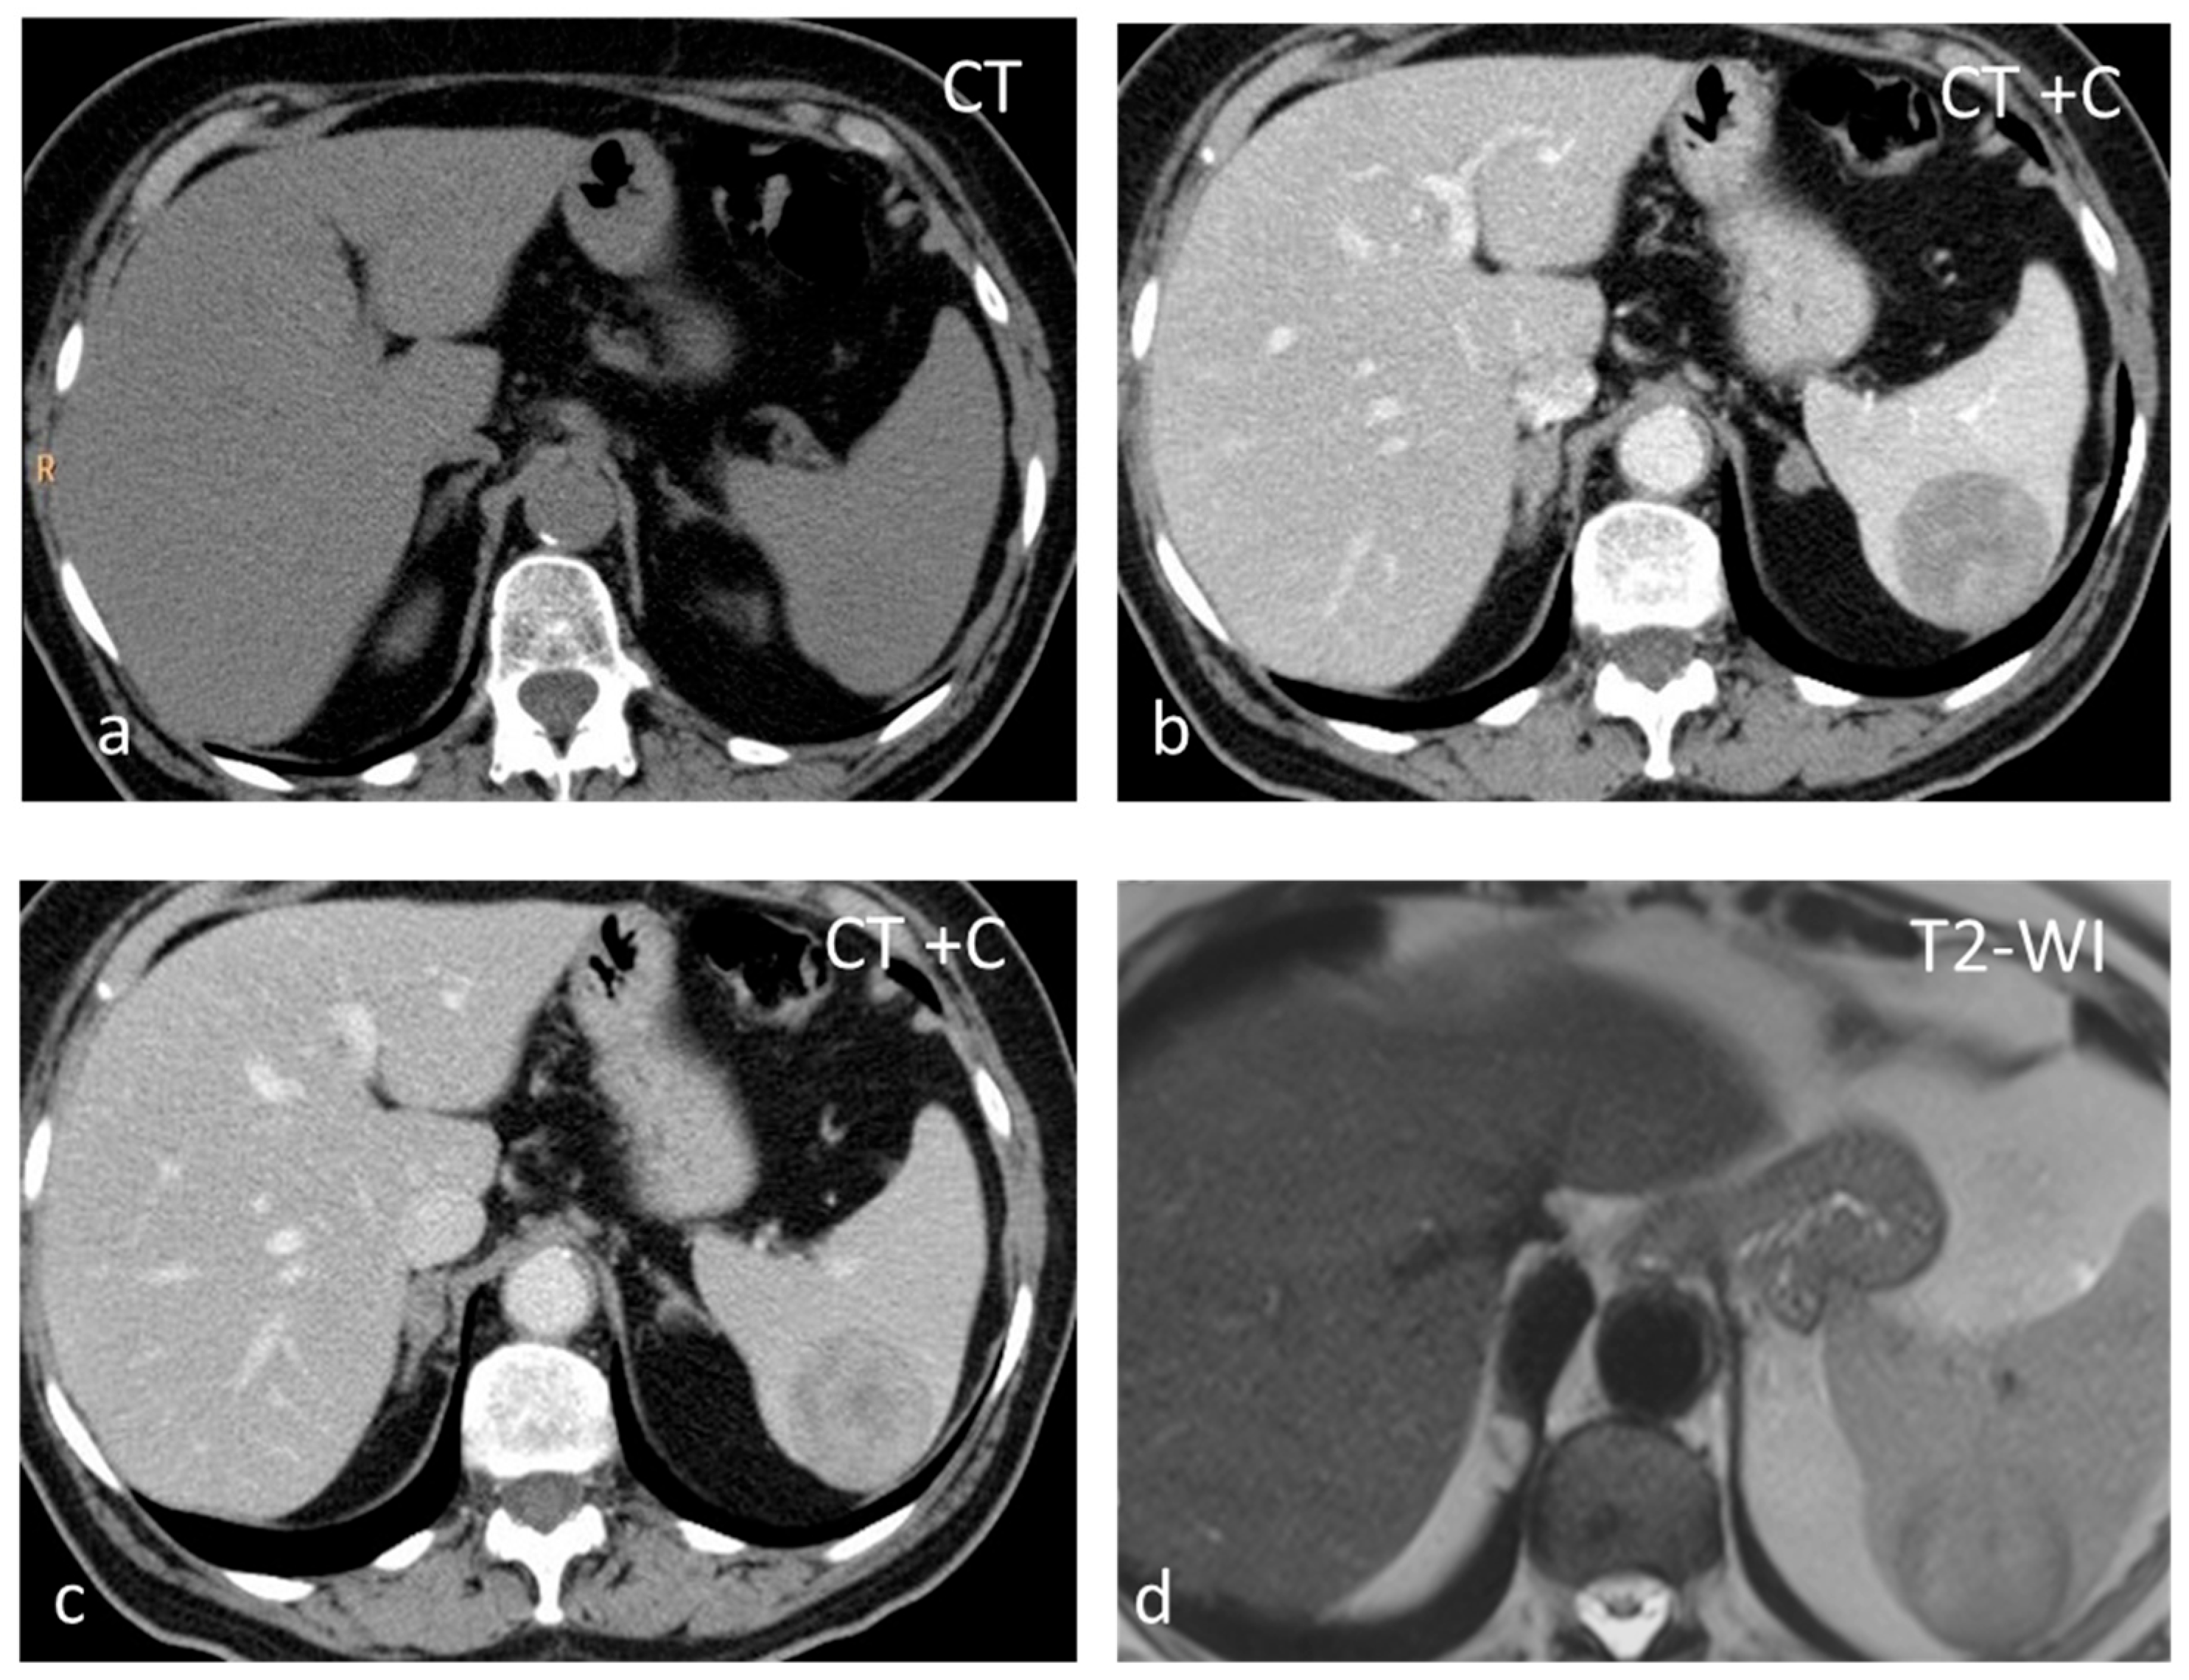

Sclerosing Angiomatoid Nodular Transformation (SANT) is a rare benign vascular disorder of unknown cause, with the same prevalence as inflammatory pseudotumors and approximately 170 cases described in the scientific literature. SANT is almost exclusively described in the spleen, except for one reported in the adrenal gland [41]. Half of SANTs are asymptomatic, and half are diagnosed because of abdominal pain, pancytopenia, and splenomegaly. SANT is considered a disease of slight female preponderance. The patients usually present in the 30- to 60-year age group. Splenectomy is a useful and effective technique for the management of SANT. SANT patients have a good prognosis, with no recurrence after splenectomy [42]. SANT is formed by multiple coalescing angiomatoid nodules from the red pulp embedded within a dense fibrous stroma [42]. The nodules are constituted by irregular vascular spaces lined by thick endothelial cells; the fibrous bands coalesce to form a central stellate fibrous scar. SANT appears as a well-circumscribed, solitary round mass, typically 3–17 cm in size. It is often mistaken for a sclerosed hemangioma or an inflammatory pseudotumor and can mimic a malignancy [41]. On CT, they present as iso- to hypoattenuating masses, while they appear isointense on T1-WI but can show areas of hyperintensity or susceptibility if a hemorrhage is present. T2-WI shows a heterogeneous, predominantly hypointense mass with hyperintense septa radiating toward the center (Figure 7). Contrast enhancement may be peripheral with radiating lines (spoke-wheel pattern), rim-like, and progressive. In the delayed phase, SANTs appear homogeneous. Moderate and heterogeneous 18F-FDG avidity has also been reported [43].

Figure 7.

SANT appearing slightly hypodense on non-contrast CT (a) and isointense on T1-WI (b), with small areas of hyperintensity due to hemorrhage. On T2-WI (c), the lesion is heterogeneous, predominantly hypointense, with hyperintense radiating septa. After gadolinium administration, enhancement is progressive (c–f) along the radiating septa converging toward the center of the lesion.